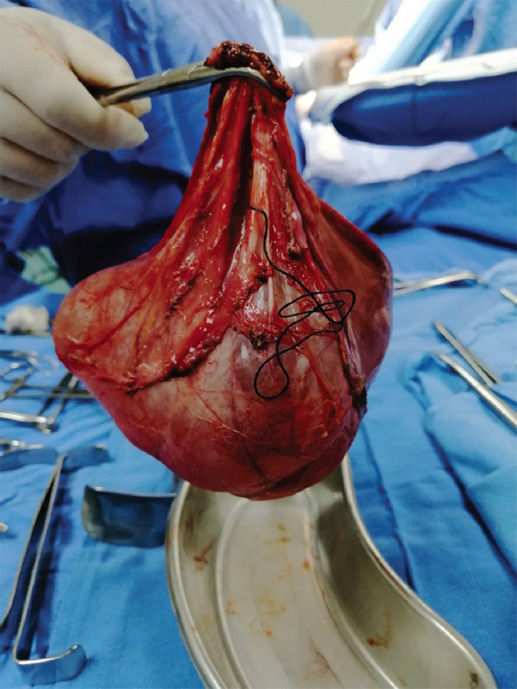

Por los resultados de la exploración física y la TC con impresión diagnóstica de cistoadenoma seroso, al tener sospecha de un componente probablemente maligno y acorde a los recursos de hospital de segundo nivel, se optó por un abordaje abierto y se realizó laparotomía exploratoria con salpingooforectomía derecha (Figs. 3 y 4), con sangrado de 50 cc durante el procedimiento, sin complicaciones. Se deja a la paciente en vigilancia, comenzando dieta a las 8 horas, y es egresada sin complicaciones a las 24 horas del procedimiento.

El estudio histopatológico reporta tejido quístico de 17 × 17 × 3 cm, superficie externa lisa de color marrón claro brillante, con líquido transparente en su interior; la superficie interior de la cápsula también de color marrón claro, consistencia suave, superficie lisa y vascularizada; en la pared interna del quiste se encuentra estroma revestido por células epiteliales cilíndricas, sin excrecencias ni pleomorfismo; no se encuentran células neoplásicas malignas en el material estudiado. Se integró el diagnóstico de quiste simple parasalpíngeo derecho.